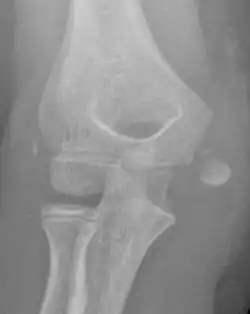

Medial epicondyle fracture of the humerus

The diagnosis is confirmed with X-rays and occasionally with a CT scan.

In all injuries to the medial epicondyle, radiographs (x-rays) are imperative. Computed tomography scans are occasionally useful in evaluating the degree of fracture displacement or the involvement of the joint surface.